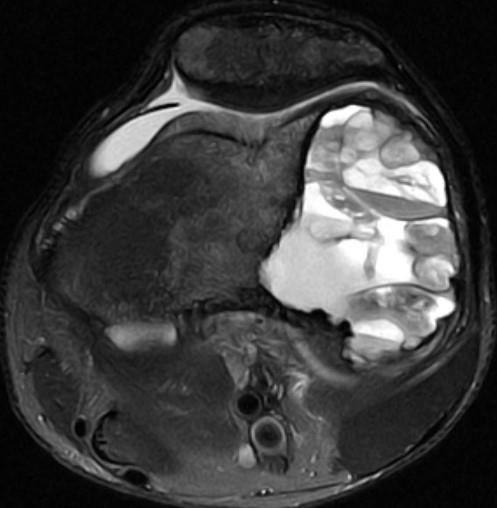

| BONE TUMORS

MRI 分析

• 病人年龄 Patient age

• 骨病变的位置 Skeleton Location

• 边缘 Margins

• 影像矩阵 Matrix